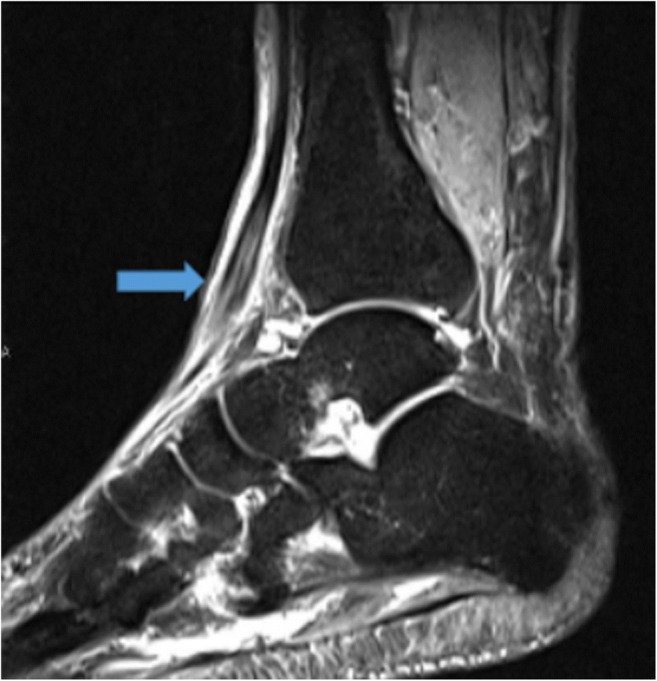

MRI provides superior soft tissue resolution and multiplanar capability to illustrate FHL tendinopathy and commonly associated posterior ankle impingement syndrome (PAIS). PAIS causes limited range of motion, specifically limited ankle plantarflexion as a result of soft tissue or bone impediment [62, 70]. MRI can delineate the posterior capsular thickening and enhancement within the musculotendinous junction of the FHL muscle belly [62]. Additionally, FHL tendinopathy can be diagnosed by visualization of an abrupt cessation of fluid around the FHL tendon at the level of the posterior talus (Fig. 9a, b) [62].

Fig. 9.

Coronal T1-weighted (a) image demonstrates increased signal within an enlarged flexor hallucis longus (FHL) tendon near its insertion (arrow), indicative of FHL tendinopathy. Sagittal T2 short-tau inversion recovery (STIR) (b) image demonstrates irregular, lobulated fluid in the proximal FHL tendon sheath (arrow) indicative of mild tenosynovitis.